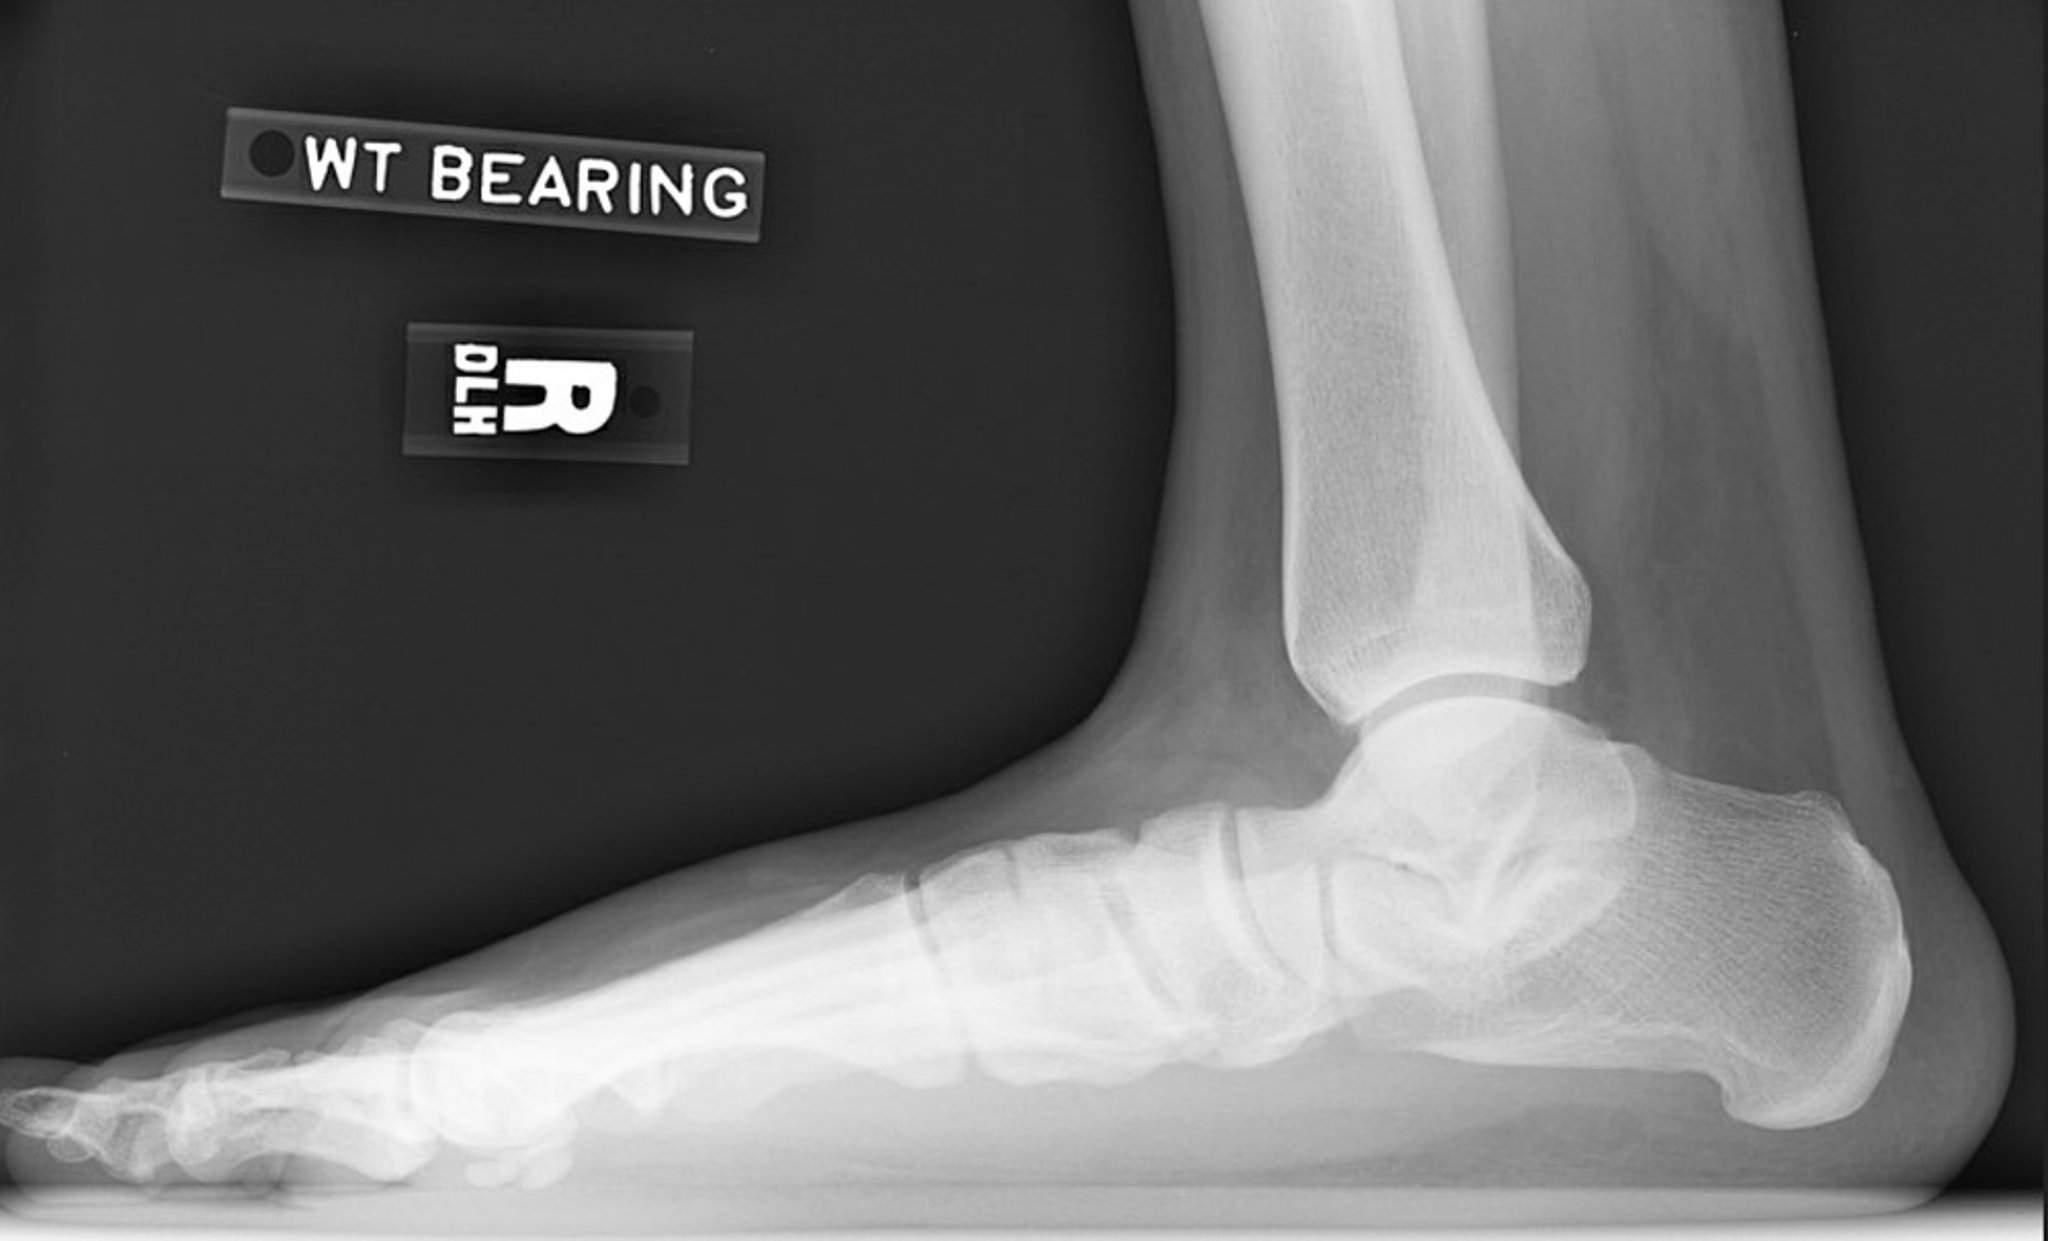

Flat Foot Radiograph

Lateral radiograph of right foot showing loss of arch height. Note the decreased calcaneal inclination angle and decreased talar declination angle. The subtalar joint is narrowed but the ankle joint is relatively preserved.

Image courtesy of James C. Connors, DPM.